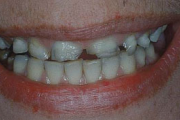

kaaries igemeäärel

kaaries